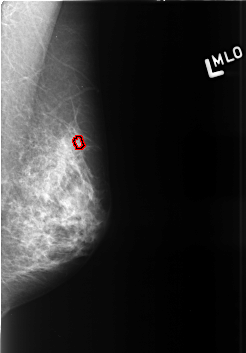

B_3426_1.LEFT_MLO

LEFT_MLO LINES 4232 PIXELS_PER_LINE 2944 BITS_PER_PIXEL 12 RESOLUTION 50 OVERLAY

FILE: B_3426_1.LEFT_MLO.OVERLAY

TOTAL_ABNORMALITIES 1

ABNORMALITY 1

LESION_TYPE CALCIFICATION TYPE ROUND_AND_REGULAR-PLEOMORPHIC DISTRIBUTION CLUSTERED

ASSESSMENT 4

SUBTLETY 3

PATHOLOGY BENIGN

TOTAL_OUTLINES 1